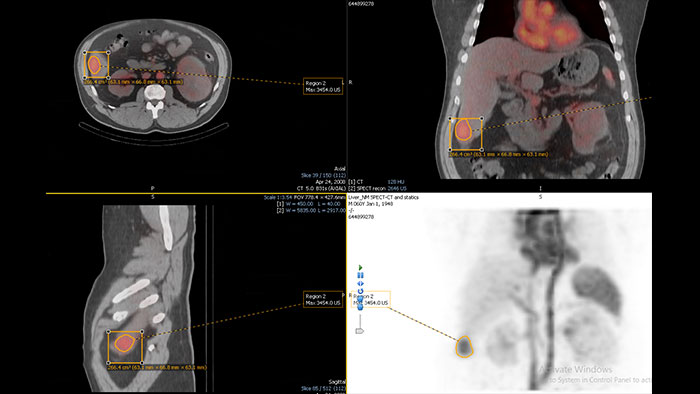

- MI Fusion

CT-MI Fusion

Fusing cardiac CT-MI images

Cardiac CT-MI Fusion incorporates support for myocardial perfusion imaging (MPI).

Benefits

- Allows loading both gated and un-gated rest, and gated and

un-gated stress MI datasets simultaneously with the CT. - The MI images are displayed in the short axis and the two long axis planes.

- The axes definition is derived from the CT study.

- Allows loading both gated and un-gated rest, and gated and